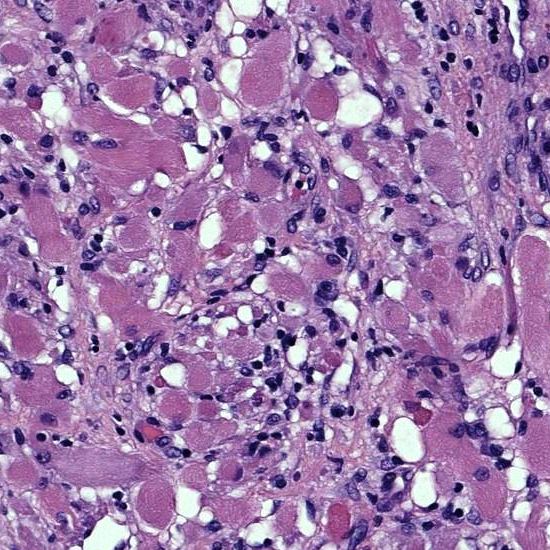

Definitive diagnosis of liposarcoma is made by pathology showing malignant proliferation of adipose tissue.

Lipoblasts are the characteristic cells seen in liposarcoma.